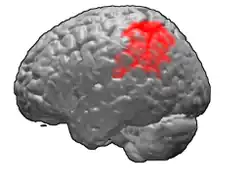

Brodmann area 40 (BA40) is part of the parietal cortex in the human brain. The inferior part of BA40 is in the area of the supramarginal gyrus, which lies at the posterior end of the lateral fissure, in the inferior lateral part of the parietal lobe.

It is bounded approximately by the intraparietal sulcus, the inferior postcentral sulcus, the posterior subcentral sulcus and the lateral sulcus. It is bounded caudally by the angular area 39 (H), rostrally and dorsally by the caudal postcentral area 2, and ventrally by the subcentral area 43 and the superior temporal area 22 (Brodmann-1909).